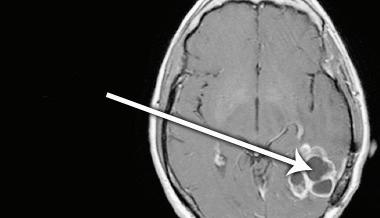

Anaplastic ependymoma

4th ventricular ependymoma, pediatric patient, T1 weighted with contrast